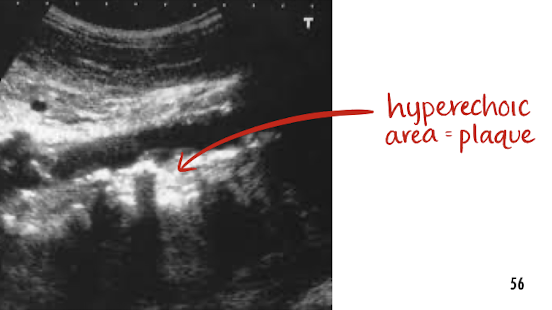

atherosclerosis

a form of arteriosclerosis

a buildup of plaque along arteries wall

must note in preliminary report if seen